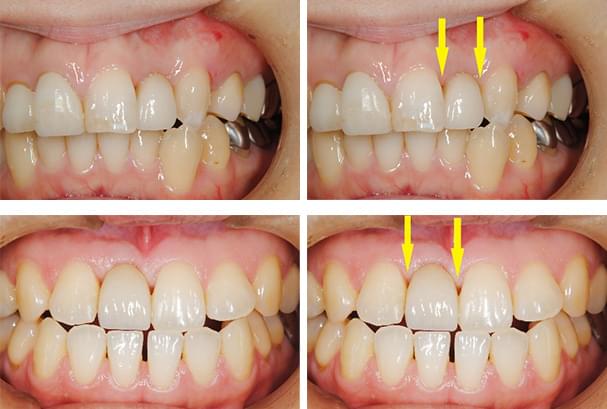

下の写真ですが、上顎前歯2本のうち向かって右の歯がインプラントなのですが、歯肉がわずかに上にあがってしまい、全くの左右対称にはできずに、右の歯の方が少し長くなってしまっています。

1歯35万円(税込38万5000円)のわけ

これなどは、もう少し長くなっていますが、口唇を上に引っ張らない限りはそれが見えません。

以下も、一見それほど問題にならない程度には仕上がっていますが、隣の歯との間、歯肉の間に空間が残っており、中にはご満足いただけないこともあります。幸いにして、この患者様方には、あらかじめ、見た目についてのご説明をさせていただいた上で、治療を始めていますので、ご納得いただいております。

審美性をさらに高め、天然歯とまったく区別ができない様にしようと思えば、追加の費用をいただいて、歯肉の移植術を行なうなど、方法はありますが、その患者様のお考えになるレベルが様々で、ご満足いただけない場合もあり、当院では、非常に高度な審美性はお約束できないと、ご説明させていただいています。